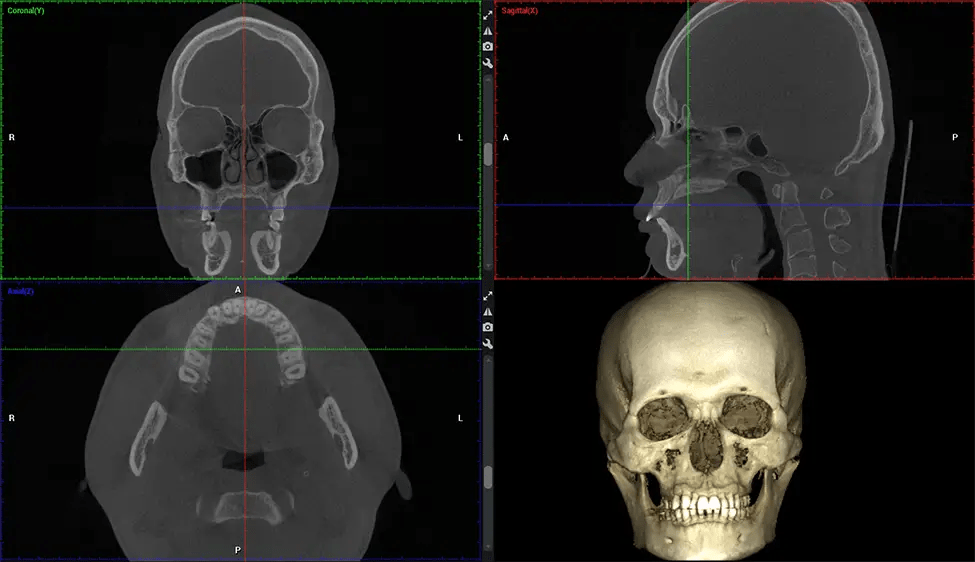

Cone Beam Computed Tomography (CBCT) is an advanced imaging technique used in dentistry and maxillofacial surgery to obtain detailed 3D images of the oral and maxillofacial structures. At Dr G Dental Studio, our CBCT scanners utilize a cone-shaped X-ray beam and a specialized detector to capture images from different angles. A computer then combines these images to create a 3D representation of the patient’s oral anatomy.

This 3D scan, called cone beam computed tomography, gives your dentist a more complete image of your oral anatomy and disease processes than a traditional X-ray. Unlike conventional X-rays, which capture a 2D image of your mouth from various angles, a 3D scan takes multiple digital X-rays for one image. It provides a complete view of your jaw, teeth, nerves, and soft tissues. This enhanced view allows dentists to detect minor issues not visible in traditional 2D scans, such as impacted wisdom teeth or bone fractures in the sinus cavity.

There are many benefits to using CBCT technology, especially compared to the traditional 2D X-ray format. One of the most significant advantages of CBCT scans is that they provide much more information than traditional X-rays. A scan lets your dentist see images from all angles of your jaw and mouth, including your sinuses, nasal cavity, cheekbones, and other surrounding areas. This added information helps your dentist craft a comprehensive treatment plan that addresses all aspects of your oral health.

Another significant benefit is that 3D imaging provides more precise images of your bone structure. These images are more detailed, providing you with a more accurate diagnosis. An accurate diagnosis means better treatment for you.